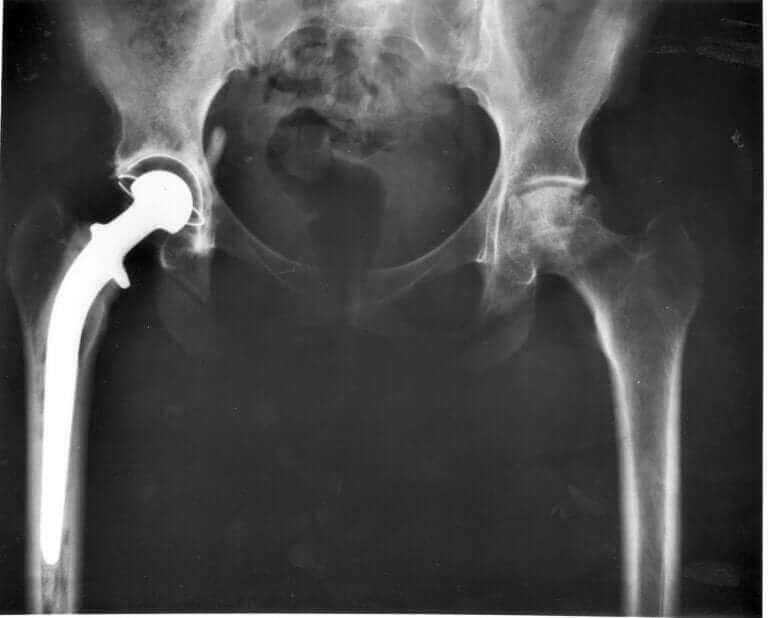

Din veterinär måste titta på kattens höftled och ta röntgen på bäcken för att identifiera det exakta problemet. Om din katt faktiskt har höftledsdysplasi så finns det några behandlingar som kan ge den lättnad och även bromsa symtomen.

I mer allvarliga fall kan det behöva en operation för att få höften ersatt.